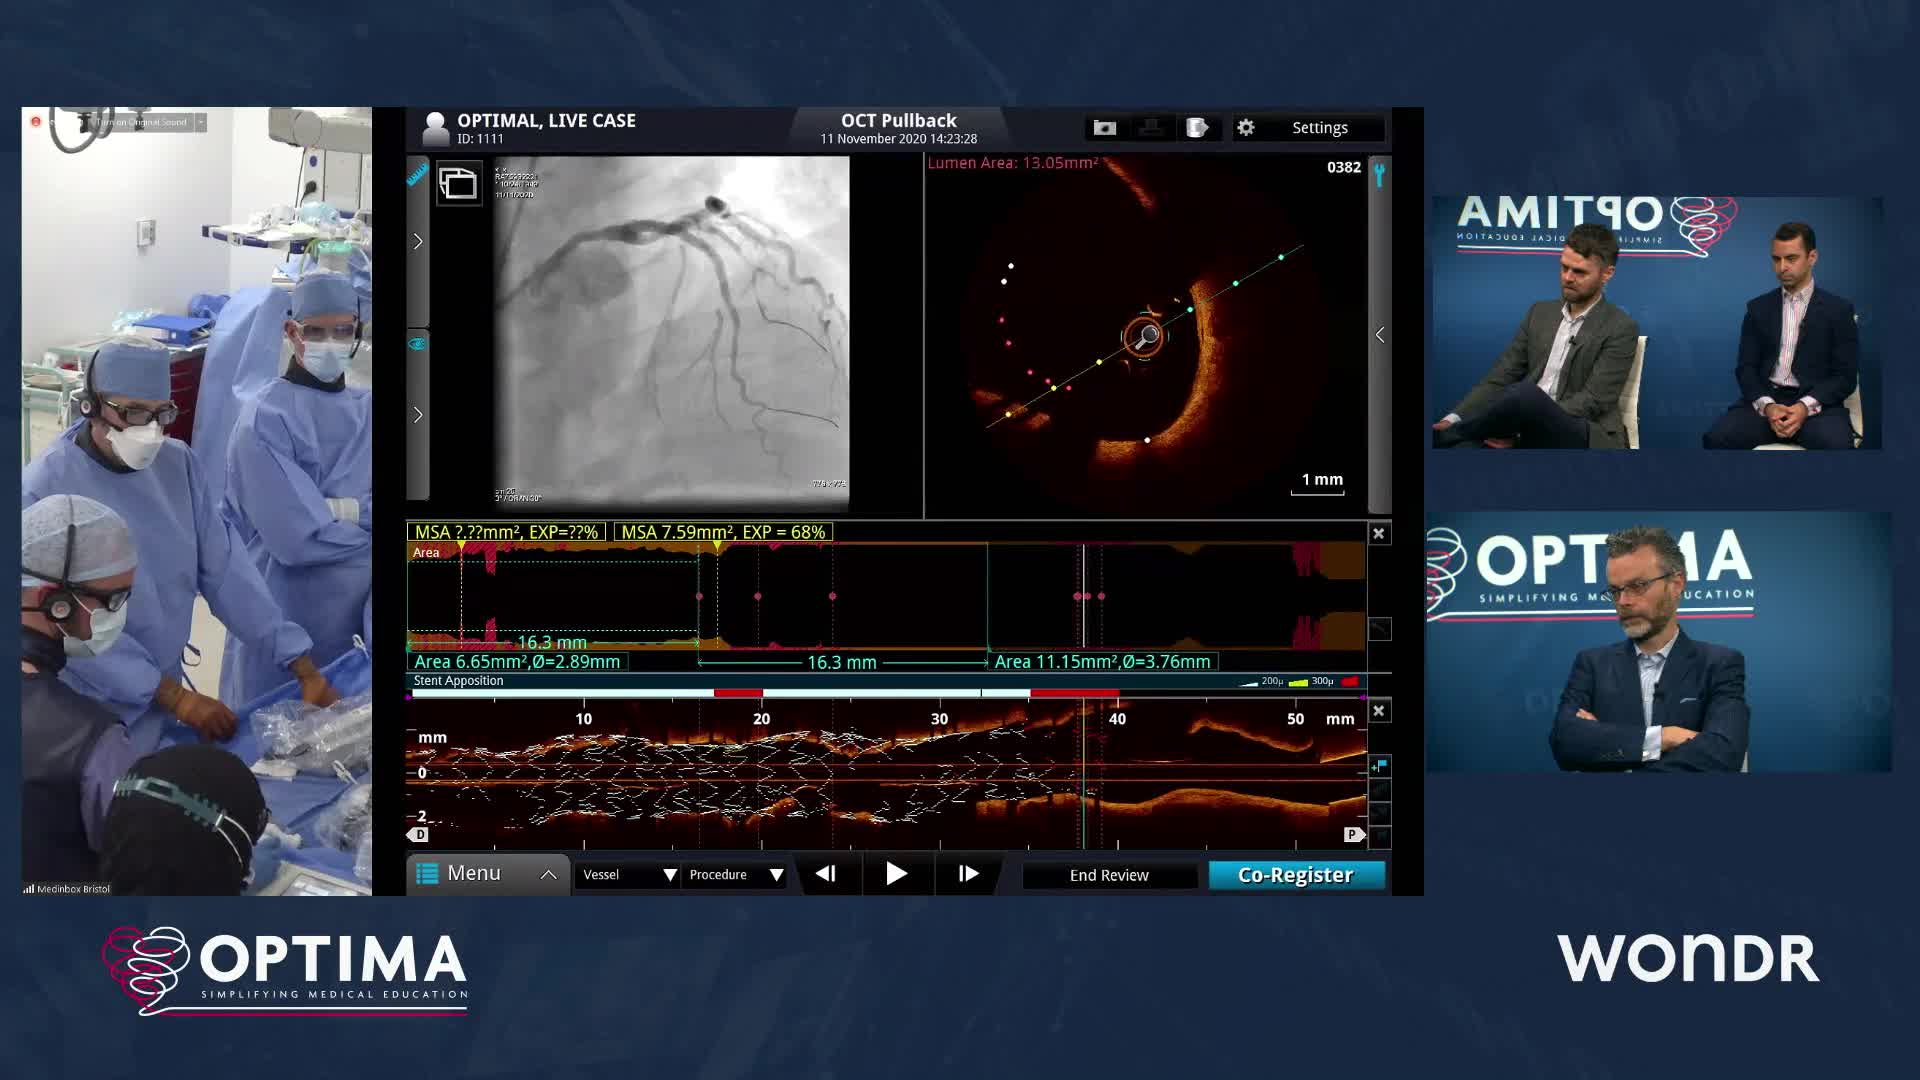

Optimal Online 2020 - Day Three

The integrated use of physiology and imaging is transforming the treatment of complex bifurcation disease. We explore...